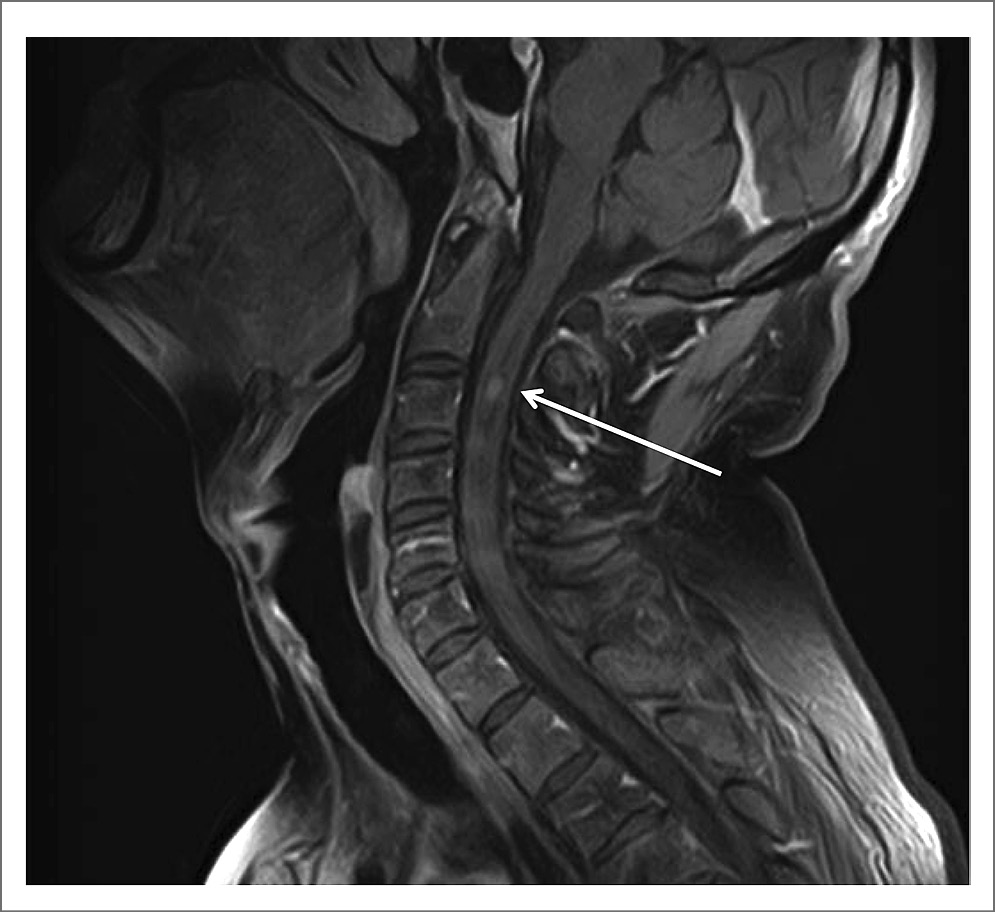

Для уточнения диагноза провели МРТ ГМ и спинного мозга. При исследовании ГМ отмечены единичные мелкие очаги в белом веществе и небольшие зоны лейкоареоза, отражающие микроангиопатию. МРТ-исследование спинного мозга в режимах T2-взвешенного изображения и FLAIR выявило протяженные участки повышенного МР-сигнала (на уровне шести шейных позвонков), заметное утолщение и неоднородную структуру шейного отдела спинного мозга, вероятно, воспалительного генеза (рис. 1, 2). При внутривенном контрастном усилении определялось накопление контрастного вещества в левом зрительном нерве на всем его протяжении (рис. 3) и в белом веществе спинного мозга, преимущественно в области задних столбов с переходом на нижнезадние отделы продолговатого мозга – зона аrea postrema (рис. 4).

Рис. 1. Изменения в шейном отделе спинного мозга на Т2-взвешенных изображениях в сагиттальной проекции (показано стрелкой).

Клинические проявления миелита при ОНМ чаще всего описывают как синдром полного поперечного поражения спинного мозга, распространяющийся более чем на 3 позвонка. Однако не исключается возможность и частичного поперечного повреждения спинного мозга [4, 10]. Такая избирательность не может не отразиться и на клинической картине миелита. У нашего больного ведущими были гипертонус в мышцах шеи, плечевого пояса, нарушение суставно-мышечного чувства в руках с гиперкинезами в кистях, напоминающих хореоатетоз. МРТ-исследование выявило парциальное вовлечение в патологический процесс задних столбов на шейном уровне с преимущественным повреждением клиновидных пучков Бурдаха (см. рис. 2). Эти канатики являются проводниками глубокой чувствительности от рук, плечевого пояса и шеи, а также несут неосознаваемые проприоцептивные импульсы от заднего спинно-мозжечкового тракта к коре червя мозжечка через его нижнюю ножку [24].